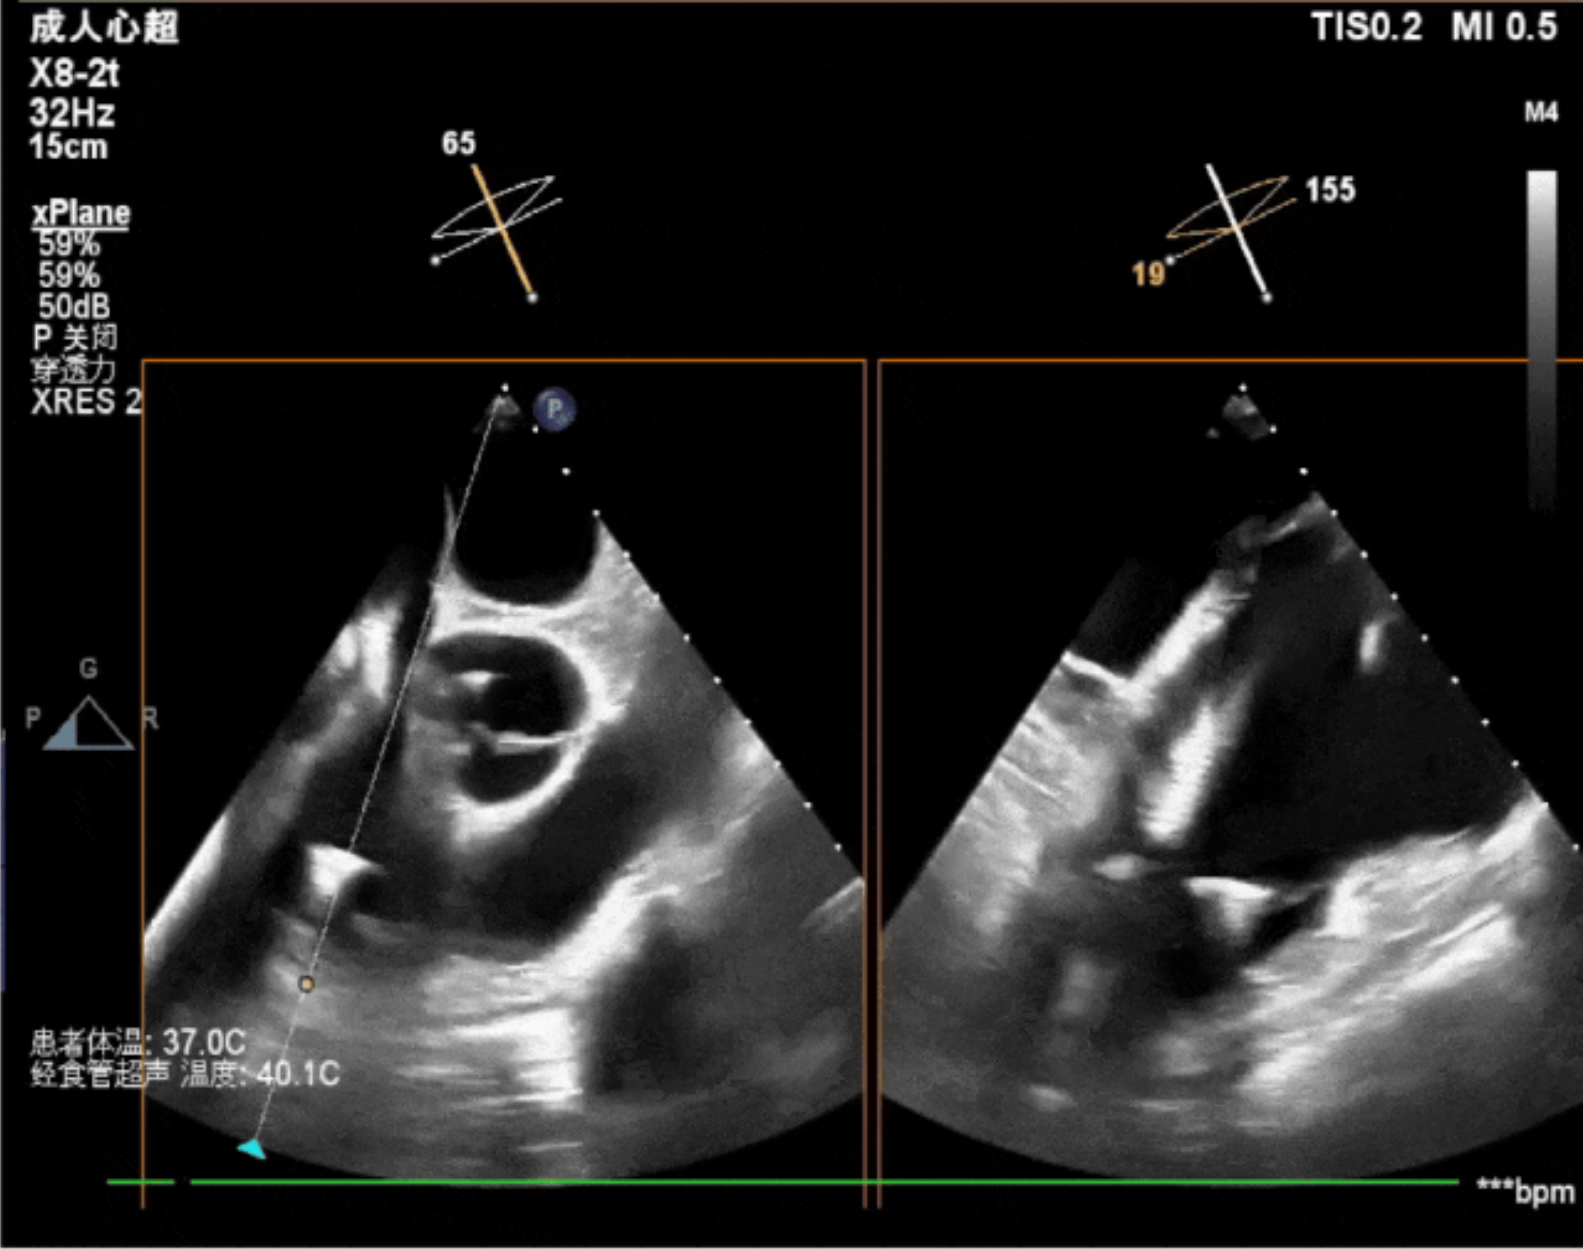

術中經食道超聲輔助下可見LuX-Valve Plus夾持件抓捕瓣葉狀態(tài)良好,夾持件在位,室間隔錨定位置良好,假體瓣膜整體錨定狀態(tài)穩(wěn)固。

術后即刻經食道超聲可見,三尖瓣假體瓣膜位置合適,牛心包瓣葉運動狀態(tài)良好,開閉正常,瓣周及瓣葉對合緣處未見明顯返流,心電圖及心包狀態(tài)較術前無明顯變化。

本次直播手術中,手術團隊在超聲與DSA等多維影像手段的支持下,精準嫻熟的完成LuX-Valve Plus瓣膜的植入,器械操作時間僅為30分鐘,瓣膜植入后術中即刻三尖瓣返流消失,多普勒超聲下無明顯瓣周漏或中心性返流,肺動脈壓正常,平均跨瓣壓差僅為1mmHg,人工瓣膜運動正常,術后1小時內該患者即安返病房。